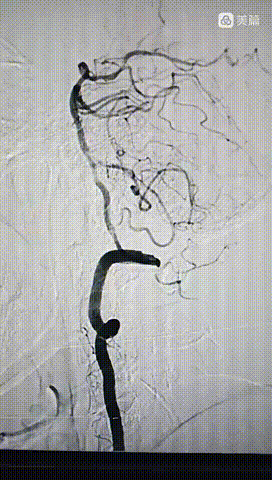

经桡动脉造影:左侧椎动脉起始终部中度狭窄。向颅内供血缓慢,v4段闭塞。

右侧椎动脉为优势椎,血流迟滞,V2以远未显影,考虑V4 闭塞。

右侧椎动脉顺应,更换6F动脉鞘经桡动脉入路行基底动脉开通。